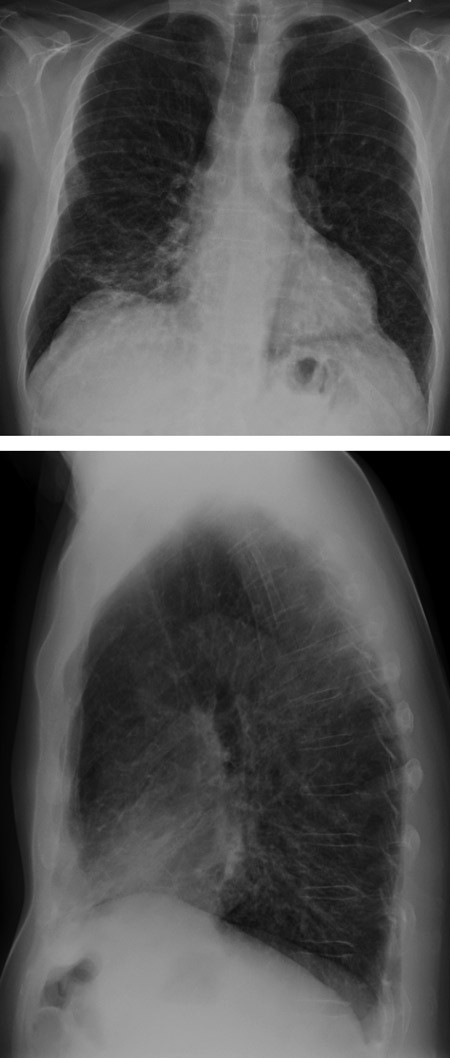

Pasienten hadde vel 20 år tidligere fått diagnosen sarkoidose basert på transbronkiale biopsier som viste granulomatøs betennelse. Ti år senere fikk han påvist immunsvikt av type vanlig variabel immunsvikt (common variable immune deficiency, CVID) og startet substitusjonsbehandling med immunglobulin. Utfall i biokjemiske leverprøver to år senere førte til leverbiopsi som viste granulomer forenlig med sarkoidose. De siste to år hadde pasienten tiltakende dyspné og respirasjonssvikt, og hadde startet med langtidsbehandling med oksygen. På henvisningstidspunktet viste arteriell blodgassanalyse (pO₂(a)) 7,1 kPa (10,0 – 14,0 kPa) med oksygen 3 l/min på nesekateter. Han trengte oksygen 8 l/min for å komme opp i pO₂ 8,0 kPa. Røntgen thorax var uendret over flere år og viste sparsomme fibrøse drag (fig 1). Spirometri var også uendret, med verdier midt i det forventede området. Gassdiffusjonskapasitet var imidlertid redusert til 48 % av forventet. Tre ukers behandling med prednisolon 20 mg daglig var forsøkt uten effekt på symptomer, lungefunksjon eller blodgasser. Han ble derfor henvist for vurdering av lungetransplantasjon, eventuelt optimalisering av behandling for sarkoidose.

Pasienten hadde i løpet av en toårsperiode utviklet respirasjonssvikt med stort oksygenbehov uten at det radiologisk eller spirometrisk var tilkommet forandringer som forklarte utviklingen. Hvis sarkoidose var årsaken, måtte forklaringen være sarkoidoseassosiert pulmonal hypertensjon. Dette kunne passe med redusert gassdiffusjonskapasitet. I henvisningen var det imidlertid anført at det var normale funn ved ekkokardiografi og at det ikke var funnet tegn til forhøyet trykk i det lille kretsløp. Det var lite sannsynlig at fibrose kunne forklare respirasjonssvikten, ettersom de radiologiske forandringene var beskjedne og han hadde normale spirometriverdier. Lungetransplantasjon er et behandlingstilbud for selekterte pasienter med kronisk respirasjonssvikt som følge av lungesykdom i sluttstadiet. Det eksisterer nasjonale og internasjonale retningslinjer for seleksjon av pasienter som kan tilbys slik behandling (1). Sarkoidose med respirasjonssvikt og eventuelt pulmonal hypertensjon er en tilstand der lungetransplantasjon kan være aktuelt. Immunsvikt er en relativ kontraindikasjon mot lungetransplantasjon. Pasienter med vanlig variabel immunsvikt som får adekvat substitusjonsbehandling og ikke har alvorlige infeksjonsproblemer, kan imidlertid aksepteres hvis de ellers fyller kriteriene og ikke har andre kontraindikasjoner.